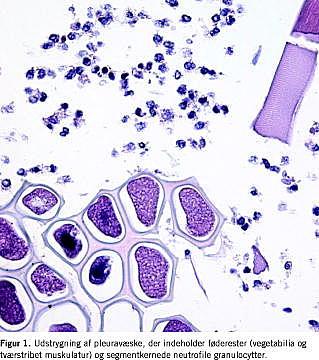

I. En 71-årig mand med asthma bronchiale blev indlagt akut med svære venstresidige brystsmerter opstået efter et kraftigt hosteanfald. Ved indlæggelsen fandt man subkutant emfysem på venstre thoraxhalvdel, diskret venstresidig pleuraekssudat, dyspnø og febrilia. På mistanke om pneumoni med empyem blev der behandlet med relevant antibiotika. Tre døgn senere viste en røntgenundersøgelse af thorax total venstresidig pneumothorax. Ved anlæggelse af pleuradræn udtømte man en tyk, brunlig væske, der ved cytologisk undersøgelse bestod af et purulent materiale med store mængder vegetabilske føderester (Figur 1 ). Syv døgn efter de primære symptomer blev der foretaget øsofagografi med vandig kontrast, hvorved der blev påvist en øsofagopleural fistel. Ved en akut venstresidig torakotomi fandt man en 15 mm lang ruptur i venstre side af den distale del af øsofagus og svært inficerede lokale forhold. Efter oprensning blev læsionen sutureret primært, og samtidig blev der gastroskopisk anlagt en covered stent (Ultraflex). På grund af lækage blev der lagt yderligere to stent, uden man opnåede tæt øsofagus, og på 27. døgn efter debutsymptomerne døde patienten.

Røntgen af thorax viser hydrothorax i 80-90% af tilfældene [1]. Påvisning af føderester eller ventrikelsekret med pH < 6, stort indhold af amylase og pladeepitelceller i det drænerede materiale vil være diagnostisk, men det er en sjældent udført undersøgelse. Diagnosen stilles i de fleste tilfælde ved øsofagografi med peroral vandig kontrast (Figur 2 ).